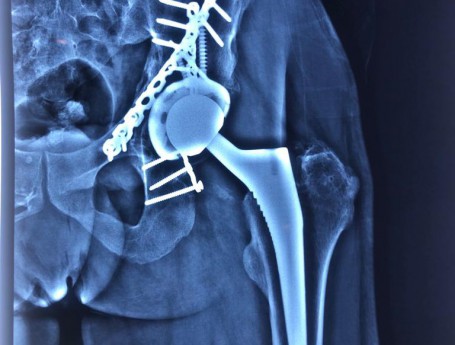

Revision Total Hip Arthroplasty Femoral Stem